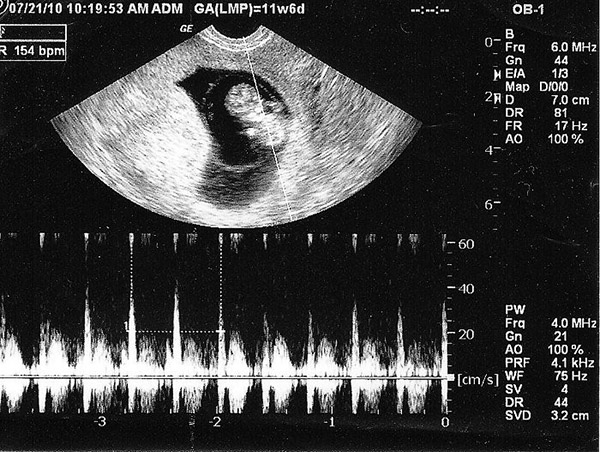

Hầu hết các chi tiết trong bảng kết quả siêu âm sẽ viết bằng tiếng Anh. Vì thế mẹ sẽ cảm thấy khá hoang mang khi cầm kết quả siêu âm trên tay. Sau đây chúng tôi sẽ hướng dẫn bạn đọc một số những chỉ số cơ bản có trong kết quả siêu âm thai 5 tuần:

– GA: Đây được coi là chỉ số biểu hiện số tuổi của thai nhi. Dấu mốc được tính từ ngày đầu của chu kỳ kinh nguyệt cuối cùng cho đến ngày siêu âm.

– GSD: Đây là chỉ số đặc biệt chỉ được biểu hiện trong những tuần đầu của thai kỳ nói lên đường kính túi thai. Khi thai đã bắt đầu hình thành các cơ quan trên cơ thể thì chỉ số này không còn được sử dụng nữa.

– BPD: Chỉ số này sẽ cho biết đường kính lớn nhất tại mặt cắt trên đầu thai nhi, hay còn được gọi là chỉ số đường kính lưỡng đỉnh.

– FL: Chỉ số biểu hiện chiều dài xương đùi của bé

– EFW: Khối lượng thai được ước tính theo máy. Đây là chỉ số quan trọng biểu thị sức khỏe của thai nhi.

– CRL: chỉ số biểu hiện chiều dài đầu-mông. Chỉ số này sẽ ngày càng chính xác hơn vào những tuần cuối của thai kỳ.

– Phôi thai và tim thai: Ở một số bà mẹ có phôi thai phát triển nhanh thì đã có thể thấy được tim thai khi siêu âm thai 5 tuần tuổi.

– Túi noãn hoàng: Khi siêu âm vào giai đoạn này thì có thể bác sĩ sẽ thấy được túi noãn hoàng của thai.

– Túi thai: Túi thai là bộ phận có chức năng bao bọc thai nhi và nước ối. Vì thế khi siêu âm thai 5 tuần tuổi, mẹ sẽ có thể nhìn thấy được túi thai một cách rõ nét.